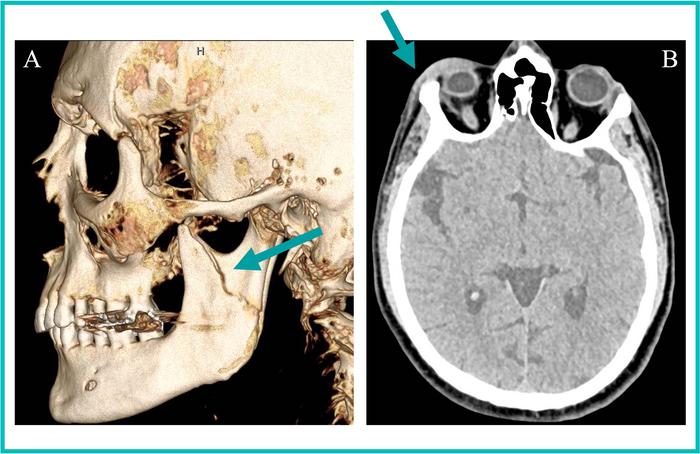

Left mandibular fracture in a 35-year-old transgender woman

35-year-old transgender woman presents with (A) a 3D CT reformation of the face in the sagittal plane showing a left mandibular fracture (arrow). (B) An axial head CT image from one of three head CT studies over the last two years revealing right periorbital soft tissue swelling (arrow). The radiologist reader suspected intimate partner violence based on radiology reports, which was subsequently confirmed through clinical note examination.

Credit: Radiological Society of North America (RSNA) and Rohan Chopra.